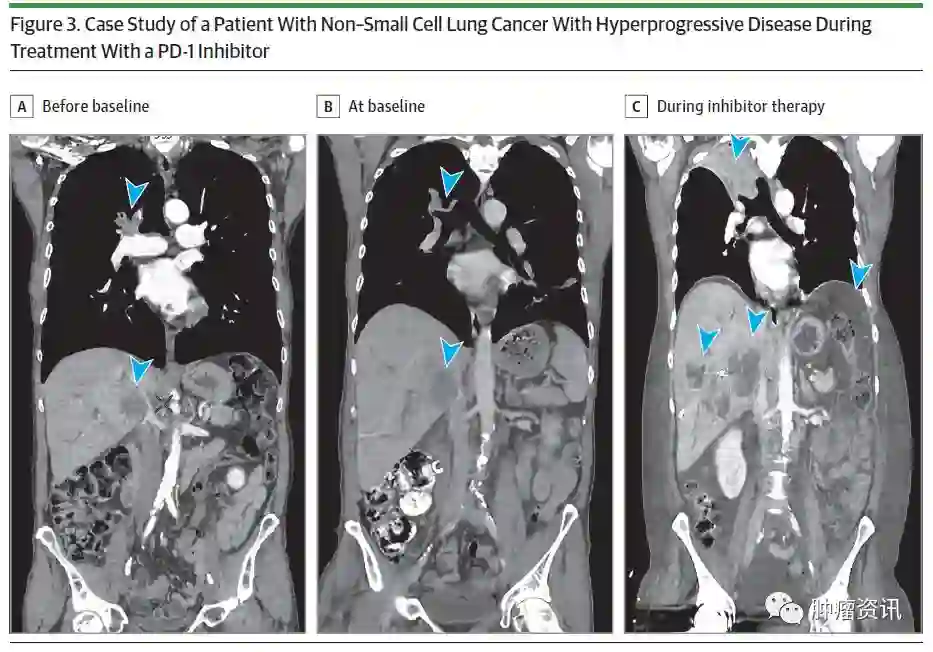

免疫治疗之前,18.5%(75/406)患者的TGR为0或更低,但由于在非靶向病灶出现新病变或进展,这些患者均被归类为疾病进展。在免疫治疗期间,TGR在266例(65.5%)患者中表现稳定或降低(ΔTGR ≤0),在140例(34.5%)患者中增加(ΔTGR >0),其中,62例(15.3%)患者最初被分类为HPD(图2A、图3)

图3.PD-1抑制剂治疗期间HPD病例分析

整体上,19例(4.7%)患者疾病进展,随后完全缓解(CR)和或部分缓解(PR)或疾病稳定超过6个月,因此这些患者被分类为假性进展,其中有6例患者最初分类为HPD,排除这6例患者,HPD率为13.8%(56例)。与非HPD患者相比,使用PD-1/PD-L1抑制剂之后,HPD与2个以上转移部位显著相关。